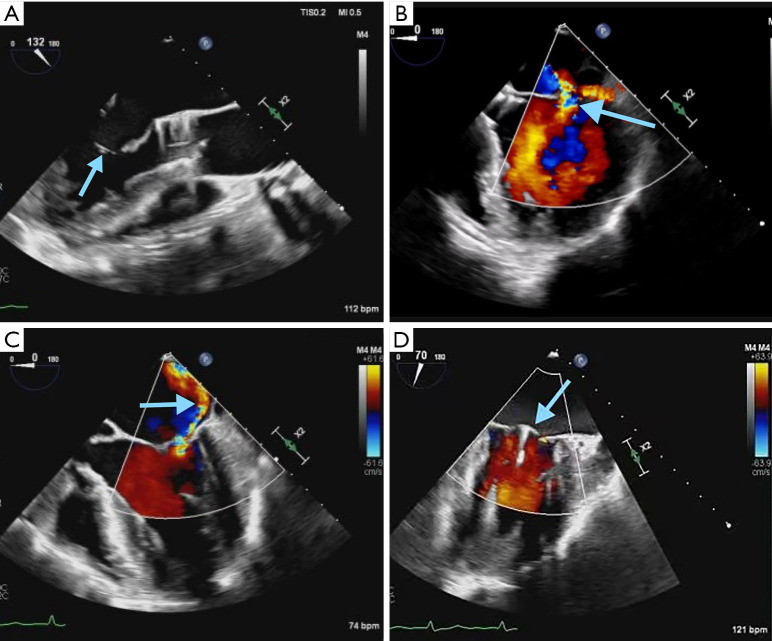

Background: There are few reports about the one-stage surgery of transcatheter aortic valve replacement (TAVR) + mitral valve transcatheter edge-to-edge repair (M-TEER) around the world. TAVR + M-TEER surgery is usually performed under the simultaneous guidance of digital subtraction angiography (DSA) and echocardiography. There is no report of TAVR surgery assisted only by echocardiography all over the world. This case shows a novel one-stage transesophageal echocardiography-guided TAVR + M-TEER surgery, which provides a new idea for minimally invasive therapy.

Case description: A 75-year-old man with recurrent chest tightness was diagnosed with bicuspid aortic valve malformation and severe regurgitation of aortic and mitral valves. The symptom was not relieved by medications. After evaluation with transthoracic echocardiography and computerized tomography angiography (CTA) of the aorta, transapical TAVR and M-TEER were performed simultaneously with satisfied clinical results. The patient's activity tolerance and cardiac function were improved.

Conclusions: In the past, this surgery needs to be performed in a specific operating room equipped with an X-ray machine, and there are many steps in the whole procedure that requires more medical staff. Transesophageal echocardiography-guided minimally invasive valvular surgery reduces the reliance on the hybrid operating room, mitigates the impact of radiation on physicians and patients, and also provides a treatment chance for gravidas with valvular disease.